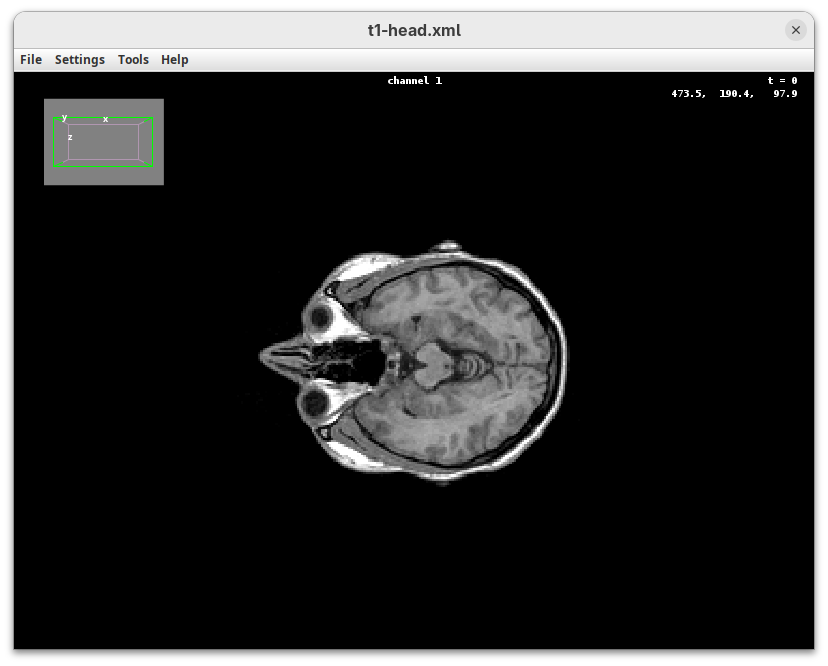

BigDataViewer

BigDataViewer (Pietzsch et al. 2015) is one of the most important tools for visualizing large, multidimensional datasets. It provides a simple and intuitive interface and shortcuts to swiftly navigate through your sample even on a regular laptop. This is possible because of the underlying file format used by BigDataViewer: the XML/HDF5 combo. Therefore, before opening the plugin, we must convert our dataset.

- Go to

Plugins>BigDataViewer>Export Current Image as XML/HDF5.

A dialog with export options will open.

- Under

Export path, click onBrowseto select the output directory fort1-head.xml.

The export process will start. Since this is a small dataset, it’ll be fast. But, for large datasets, this can take hours.

When done, you will find two new files in your working directory: t1-head.xml and t1-head.h5.

The XML file stores metadata information about the image. The HDF5 file stores actual image data. These two files will always be in a pair. To open the XML/HDF5:

- Go to

Plugins>BigDataViewer>Open XML/HDF5and select thet1-head.xml.

The BigDataViewer interface will open showing an optical section of the head sample.

Getting familiar with BigDataViewer is an essential skill for navigating large 3D datasets. It’ll also be important for the multiview registration pipeline. So, take the time to learn the basic commands and shortcuts. It is nicely intuitive. The BigDataViewer’s page on the ImageJ Docs has the official documentation and we can also go to Help > Show Help for an up-to-date overview.

Some of the movements to try:

Left-click and drag: turn the sample around the mouse pointer at any arbitrary angle.Right-click and drag: move the sample in the XY plane (of the view).Scroll: move through the Z plane (of the view). UseShift+Scrollto move fast.Ctrl+Shift+Scroll: zoom in or out.

But, most importantly, are the commands to put your sample back to its original orientation or along any of the original dimension axes:

Shift+Z: orient the sample on the XY plane.Shift+X: orient the sample on the ZY plane.Shift+Y: orient the sample on the ZX plane.

Finally, a visual tip. The default interpolation between image slices is nearest-neighbors. Press I to activate the tri-linear interpolation to obtain a much smoother (and improved) data visualization.